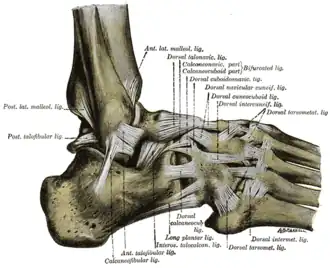

Röntgendiagnostiek is enkel geïndiceerd wanneer er sprake is van pijn in de malleoli of in de middenvoet en daarenboven een van volgende symptomen zich voordoet:

- Pijn bij palpatie van de distale 6 cm van de posterieure zijde van het scheenbeen of de knobbel van de binnenenkel;

- Pijn bij palpatie van de distale 6 cm van de posterieure zijde van het kuitbeen of het uiteinde van de buitenste enkelknobbel;